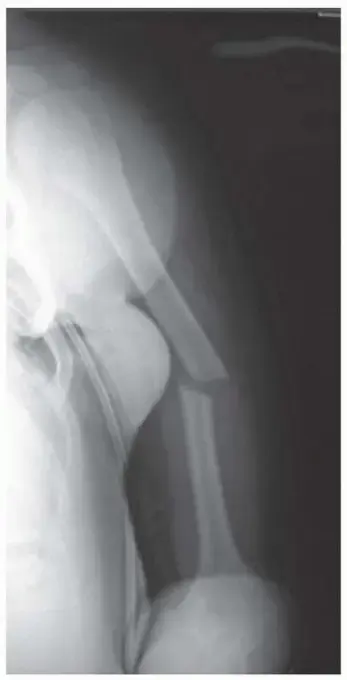

صورة توضيحية لـ إزالة الصفائح والمسامير بعد شفاء الكسور: دليلك الشامل لتعافٍ أفضل في اليمن

## هل يجب إزالة الصفائح والمسامير بعد الكسر؟ تعرضت لكسر في العظم؟ خضعت لعملية تثبيت باستخدام الصفائح والمسامير المعدنية؟ تهانينا، لقد تجاوزت المرحلة الأصعب وبدأ عظمك بالالتئام! ولكن، قد يراودك الآن سؤال حيوي ومهم يشغل بال الكثيرين: هل يجب إزالة هذه الصفائح والمسامير بعد شفاء الكسر أم يُفضل تركها داخل الجسم؟ وما هي الفوائد والمخاطر المرتبطة بكل قرار؟

في كثير من الحالات، خاصة الكسور المعقدة أو التي تؤثر على المفاصل، لا يكفي الجبس وحده لإعادة العظم إلى موضعه الصحيح والسماح له بالالتئام بشكل سليم. هنا يأتي دور الجراحة التثبيتية، والتي تعرف باسم "التثبيت الداخلي" (Internal Fixation).

الصفائح والمسامير هي أدوات جراحية دقيقة تُستخدم لإعادة قطع العظم المكسور إلى محاذاتها الطبيعية وتثبيتها بإحكام حتى يلتئم. تخيل أن عظمك المكسور هو طبق فخاري تحطم إلى قطع؛ الصفائح والمسامير تعمل كالغراء والدعامات التي تجمع هذه القطع وتثبتها في مكانها الصحيح لتلتصق مجدداً وتعود القطعة الفخارية (العظم) إلى شكلها ووظيفتها الأصلية.

• الصفائح (Plates): هي قطع معدنية رفيعة ومسطحة، عادة ما تكون مثقوبة، وتُصنع بأشكال وأحجام مختلفة لتناسب أجزاء الجسم المختلفة. تُوضع الصفيحة على سطح العظم وتُثبت بمسامير.

• المسامير (Screws): هي براغي صغيرة تُستخدم لتثبيت الصفيحة بالعظم، أو أحياناً لتثبيت قطع العظم ببعضها مباشرة.

هذه المواد تُصنع من معادن خاصة مثل التيتانيوم أو الفولاذ المقاوم للصدأ، والتي تتميز بقدرتها على التكيف مع الجسم البشري دون التسبب في تفاعلات سلبية (متوافقة حيوياً). الهدف الأساسي من هذه العملية هو توفير بيئة مستقرة لالتئام العظم، مما يضمن استعادة وظائفه الحركية بشكل كامل.